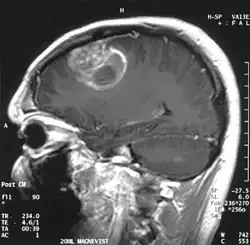

| A coronal view (from the back of the head) of a contrast-enhanced MRI revealing a glioblastoma in a 15-year-old boy | |

When viewed with MRI, glioblastomas often appear as ring-enhancing lesions. The appearance is not specific, however, as other lesions such as abscess, metastasis, tumefactive multiple sclerosis, and other entities may have a similar appearance.[61] Definitive diagnosis of a suspected GBM on CT or MRI requires a stereotactic biopsy or a craniotomy with tumor resection and pathologic confirmation. Because the tumor grade is based upon the most malignant portion of the tumor, biopsy or subtotal tumor resection can result in undergrading of the lesion. Imaging of tumor blood flow using perfusion MRI and measuring tumor metabolite concentration with MR spectroscopy may add diagnostic value to standard MRI in select cases by showing increased relative cerebral blood volume and increased choline peak, respectively, but pathology remains the gold standard for diagnosis and molecular characterization.